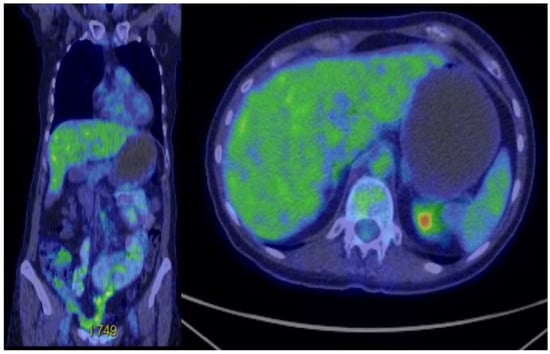

Treatment was initiated with nivolumab 480 mg every 4 weeks and cabozantinib 40 mg daily. This regimen was maintained for the first three months, with scheduled imaging assessments—including PET-CT and hepatic MRI—at 3 to 4 months to evaluate both structural changes and metabolic activity of liver and residual peritoneal metastases. Monthly clinical and laboratory follow-up was performed, during which the patient showed good treatment tolerance without adverse events. Follow-up imaging at 3 and 6 months demonstrated no disease progression on PET-CT or hepatic MRI. At the 9-month evaluation, liver MRI identified three new small lesions (measuring 5–8 mm). Two of these showed slight dimensional progression, while one showed regression compared to the previous scan. According to RECIST 1.1 criteria, the overall assessment remained consistent with stable disease. To further evaluate metabolic activity, an additional PET-CT was performed (see Figure 4). It revealed multiple nodular and flat lesions located along the anterior peritoneal surface of segments III, IV, VI, and VIII (SUV max up to 6.66; largest lesion 5.3 × 1.3 cm), as well as intraparenchymal lesions in segment V (SUV max 4.62) and segment VI (1.5 × 1.3 cm, SUV max 9.22). On PET-CT prior to treatment, the hepatic lesion had an SUVmax of 12.4, which decreased to 5.2 at 6 months and remained stable at 18 months. The maximum SUV of the largest peritoneal nodule decreased from 11.5 to 7.3 cm. These findings supported the clinical observation of durable disease control. Despite these findings, the disease remained classified as stable.

Figure 4. Treatment response on PET-CT evaluation at 9 months.